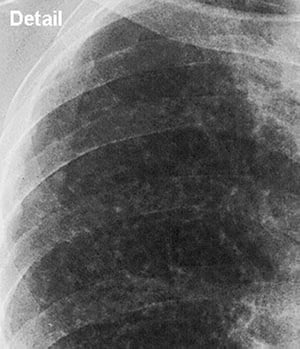

Silicosis—Simple (Upper Lung Field)

Close up view of upper lung field in simple silicosis.

Image courtesy of David W. Cugell, MD.

Chronic silicosis is categorized on chest imaging as simple or complicated. In patients with simple silicosis, there is upper lobe predominance of bilateral 1- to 3-mm reticulonodular opacities. Calcified hilar and mediastinal lymph nodes are common and occasionally resemble eggshells; however, eggshell calcification is not pathognomonic for silicosis. Pleural thickening is uncommon unless a severe parenchymal disease abuts the pleura.